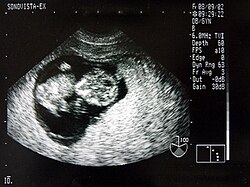

Das Ultraschallbild wird auch Sonogramm genannt.

Neben der Herztonwehenschreibung (Kardiotokografie) ist sie ein Standardverfahren in der Schwangerschaftsvorsorge. Eine spezielle Untersuchung der Pränataldiagnostik zur Erkennung von Entwicklungsstörungen und körperlichen Besonderheiten ist der Feinultraschall.

Von den Monitorbildern werden zur Dokumentation Ausdrucke, sogenannte Sonogramme, oder gelegentlich Videoaufnahmen gemacht. Schwangeren wird häufig auch ein Bild ihres ungeborenen Kindes überlassen.